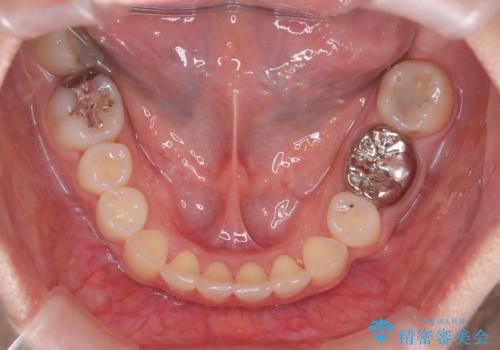

【抜歯矯正】犬歯抜歯による矯正。八重歯を治したい

- 八重歯を主訴に来院された患者様です。

抜歯矯正において、通常では4番(第一小臼歯)が抜歯の対象となることが多いのですが、今回は3番(犬歯)の歯肉退縮や装置の特性を考慮した治療計画となります。

下顎に関しては、半年ほどワイヤー矯正にてリカバリーを行なっております。